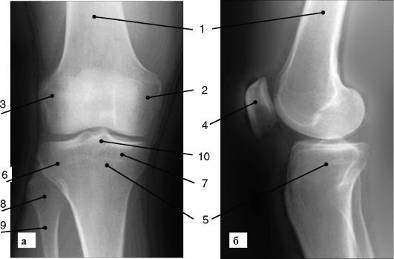

Суставы состоят из суставных поверхностей соответствующих костей и хрящевых структур. Последние на рентгенограммах не определяются. Из-за проекционного искажения суставная щель на рентгенограммах шире анатомической. Суставные концы костей четко очерчены и окаймлены плотной замыкающей (субхондральной) пластиной, которая имеет вид плотной тонкой тени. Эта тень является продолжением тени коркового слоя диафиза (рис. 6).

Рис. 6. Рентгенограмма коленного сустава (а - передняя; б - боковая проекция): 1 - бедренная кость; 2 - латеральный мыщелок бедренной кости; 3 - медиальный мыщелок бедренной кости; 4 - надколенник; 5 - большеберцовая кость; 6 - латеральный мыщелок большеберцовой кости; 7 - медиальный мыщелок большеберцовой кости; 8 - головка малоберцовой кости; 9 - шейка малоберцовой кости; 10 - межмыщелковое возвышения суставов широко используют МР-томографию и ультразвуковое исследование.